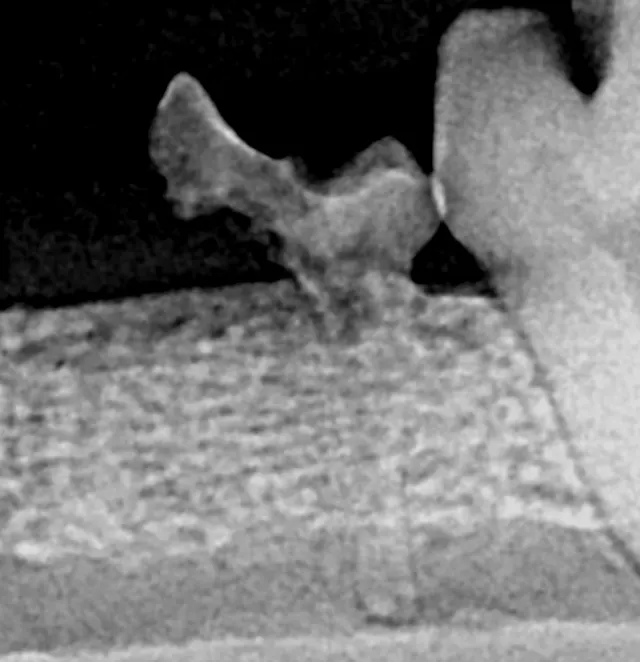

Resorption of the right maxillary canine root in a 3-year-old English bulldog.

Root canal therapy, an advanced procedure with guarded prognosis, can be used to treat cases of internal and external tooth resorption.1 Because tooth resorption in dogs is idiopathic and possibly progressive, long-term success of root canal therapy may not affect the clinical course of tooth destruction.